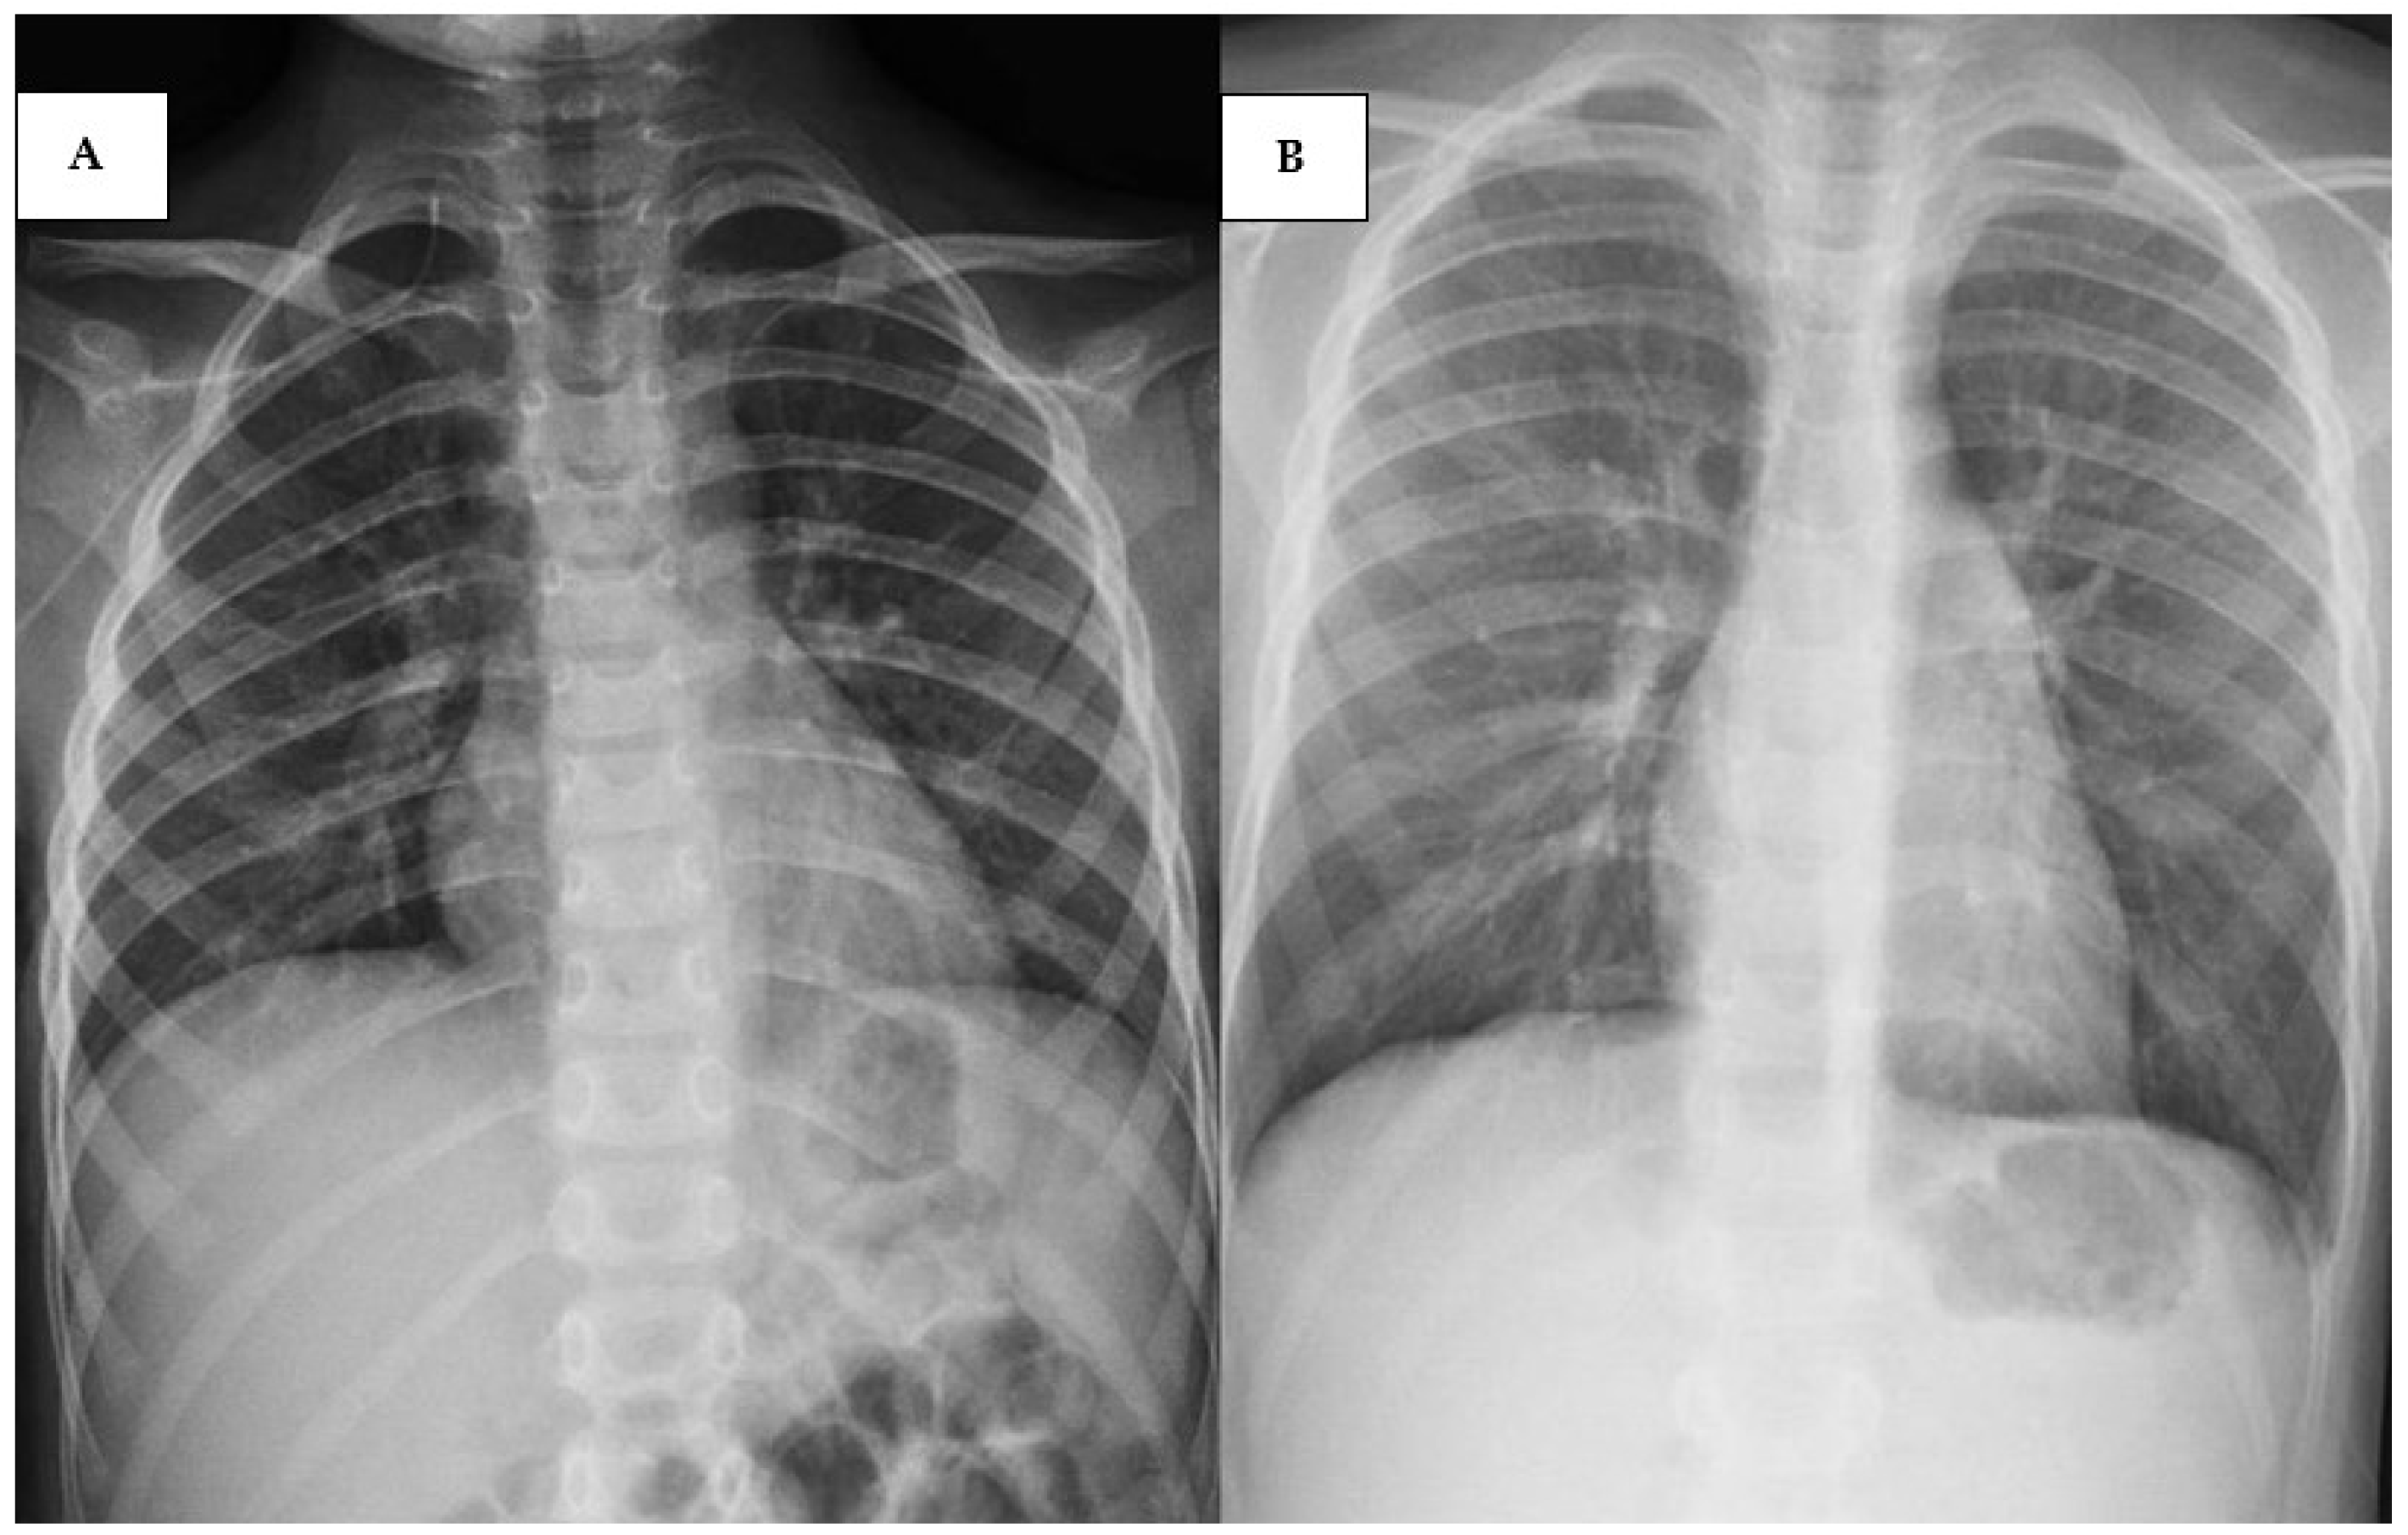

2.1. Case 1 [Unique Patient Number (UPN) 1069066]

2.2. Case 2 (UPN 1077926)